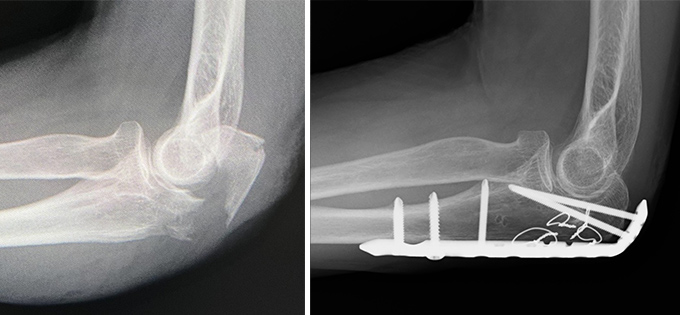

肘関節脱臼骨折(OFD・PLRI・PMRI・TTI)

脱臼に骨折や靱帯損傷を伴う複合的な肘外傷で、治療が難しい重症な外傷です。代表的なものに、肘頭脱臼骨折(OFD)、後外側回旋不安定症(PLRI)、後内側回旋不安定症(PMRI)、橈骨頭と鉤状突起骨折を伴うテリブルトライアッド(TTI)などがあります。これらは骨折と靱帯損傷の双方を正確に整復・修復しなければ、慢性的な不安定性や痛み、可動域制限を残す可能性が高いです。近年は治療戦略が構築されてきており、プレート固定やアンカーなどを用いた靱帯縫合により、安定した関節機能の再獲得が可能となってきています。

症例① 60代 女性

症例② 40代 男性